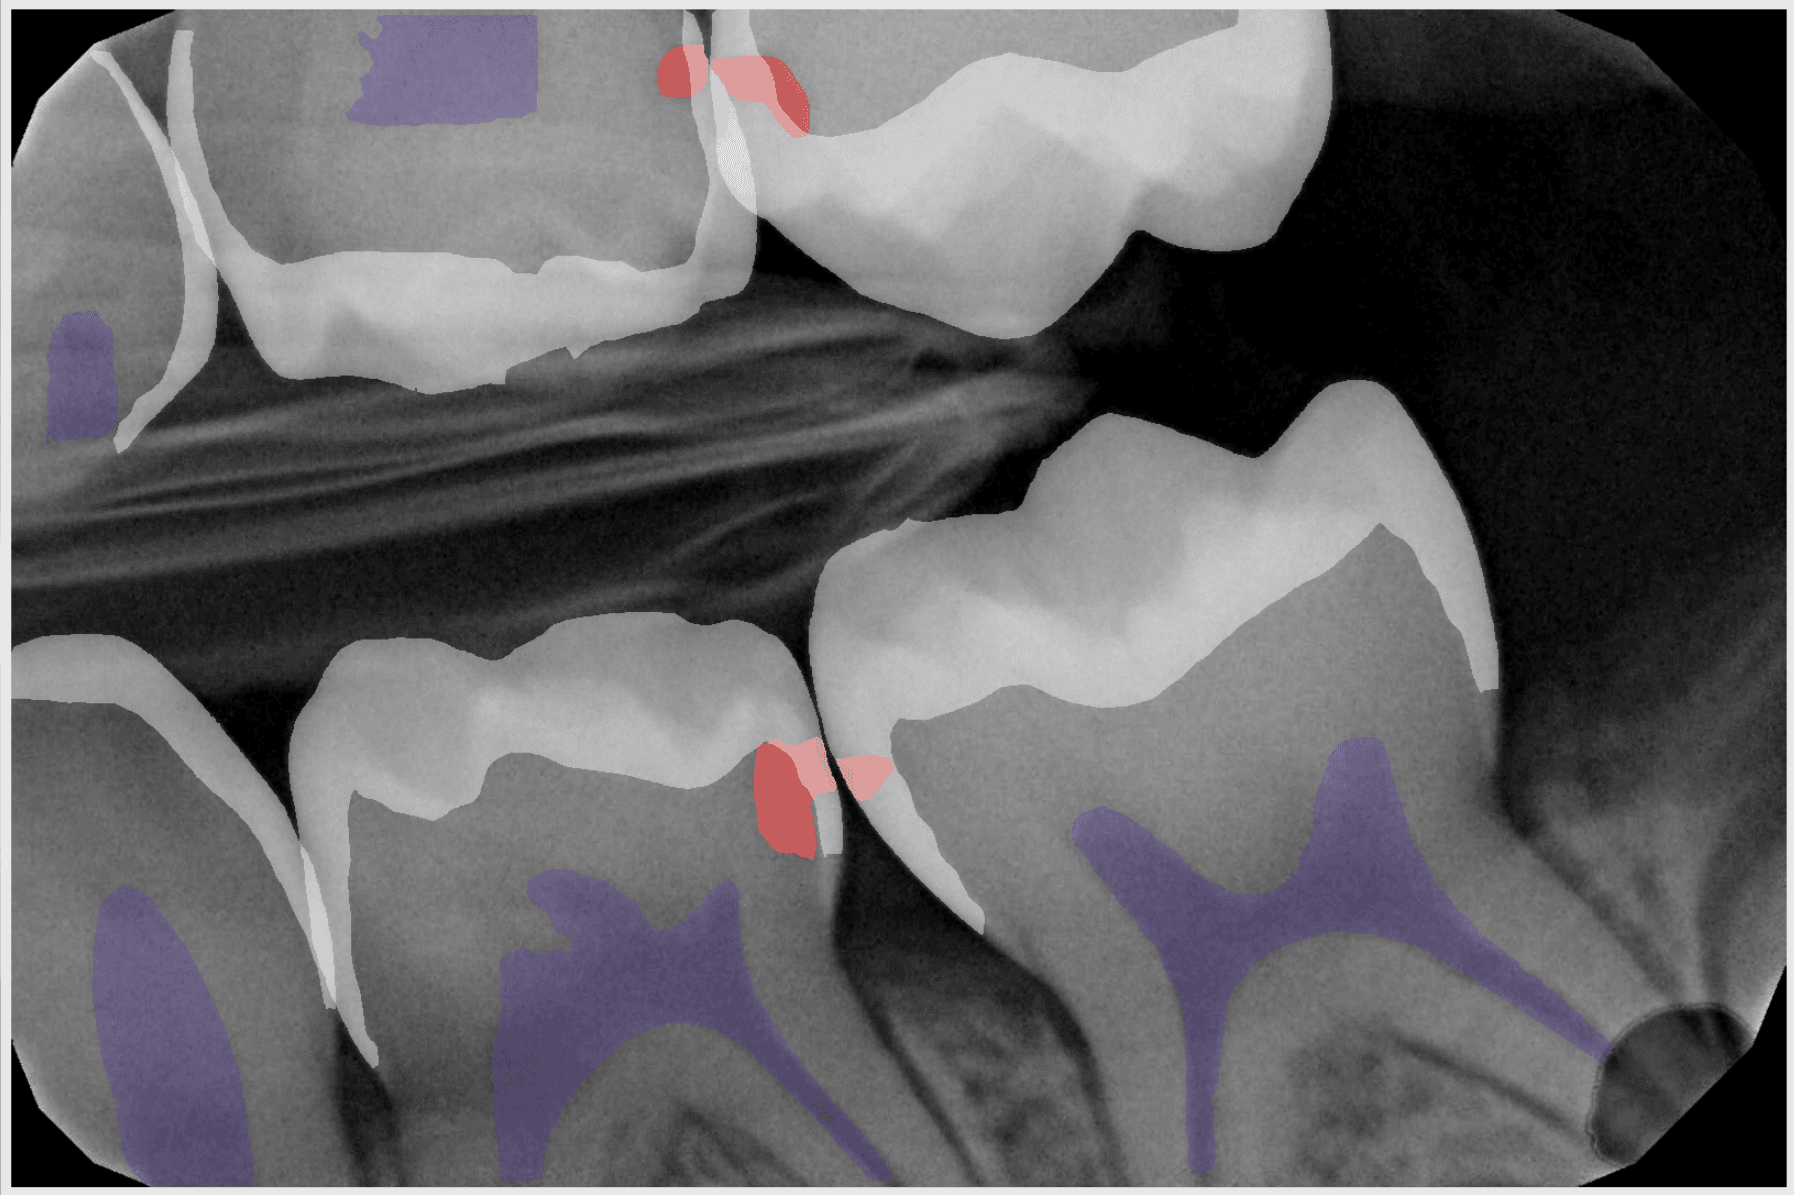

Join us for a 30-minute webinar with Dr. Robert Friedman, Clinical Director at Dental Care Alliance, as he shares how adding Overjet’s artificial intelligence for X-ray analysis to Apteryx digital imaging increases case acceptance, builds trust with patients, and streamlines operational workflows in his clinics.

Overjet is FDA-cleared to detect caries for ages 4+, measure bone levels down to the millimeter, and identify more areas of concern with precision.